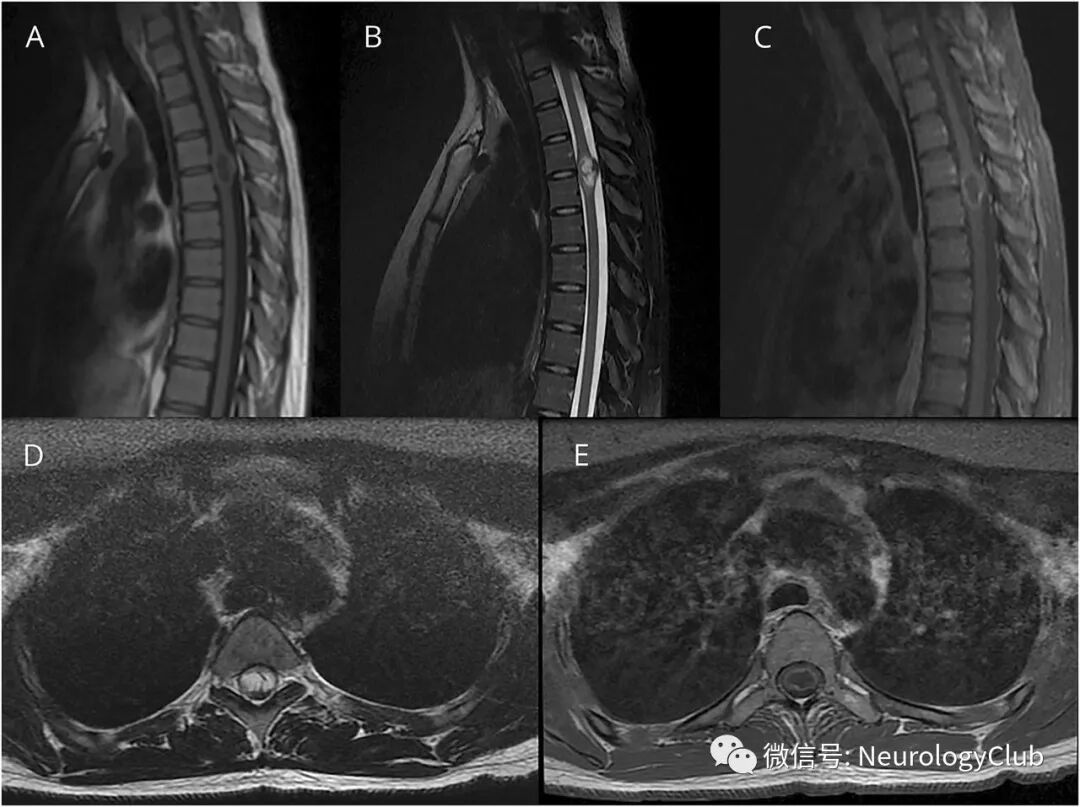

20岁女性,表现为亚急性进行性下肢无力和痉挛状态。查体提示Brown-Sequard综合征。胸椎MRI/磁共振血管造影提示髓内肿块(图1)。

(图1:A:矢状位T1WI;B:矢状位T2WI;C:矢状位T1增强;D:横断面T1WI;E:横断面T1增强;可见T4-T5水平膨胀性,周围强化病变,病灶内存在曲线样T2低信号区域,灶周水肿不明显,未发现脊髓血管畸形的证据